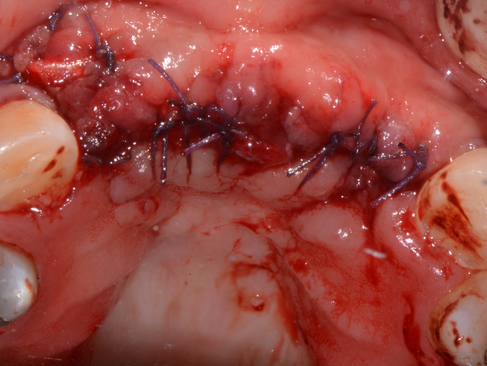

5 Months review: Dehiscence of soft tissue. Decision made to remove Ti- mesh and place implants.

Ti-mesh exposed.

Thin pseudo-periosteum covering newly regenerated bone present under Ti-mesh